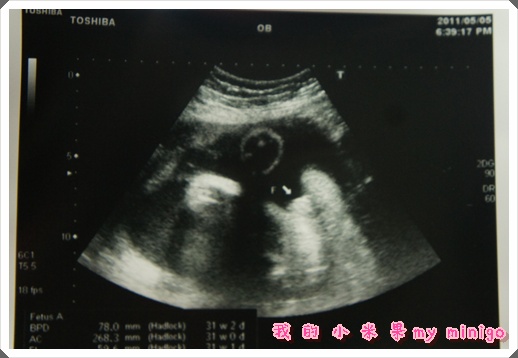

30w5d 第七次產檢

今天門診人比較多喔 我們六點十五到 已經很多媽咪們都在看診了

照往例驗尿 量血壓 體重後 直接到熟悉的邱醫生二十四室診療室